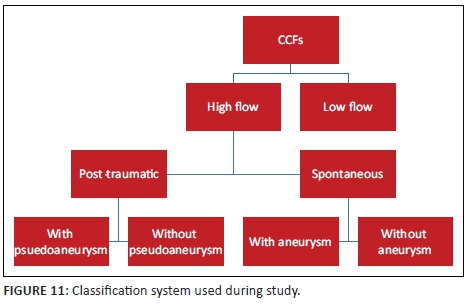

Assessing the arterial supply allows classification of the CCF by means of the Barrow's classification. This classification was found to be confusing and did not add further value in terms of further management. In our experience, classifying the fistula according to its flow dynamic and documenting the presence of an intracavernous aneurysm or pseudoaneurysm was found to be more practical (see Figure 11).